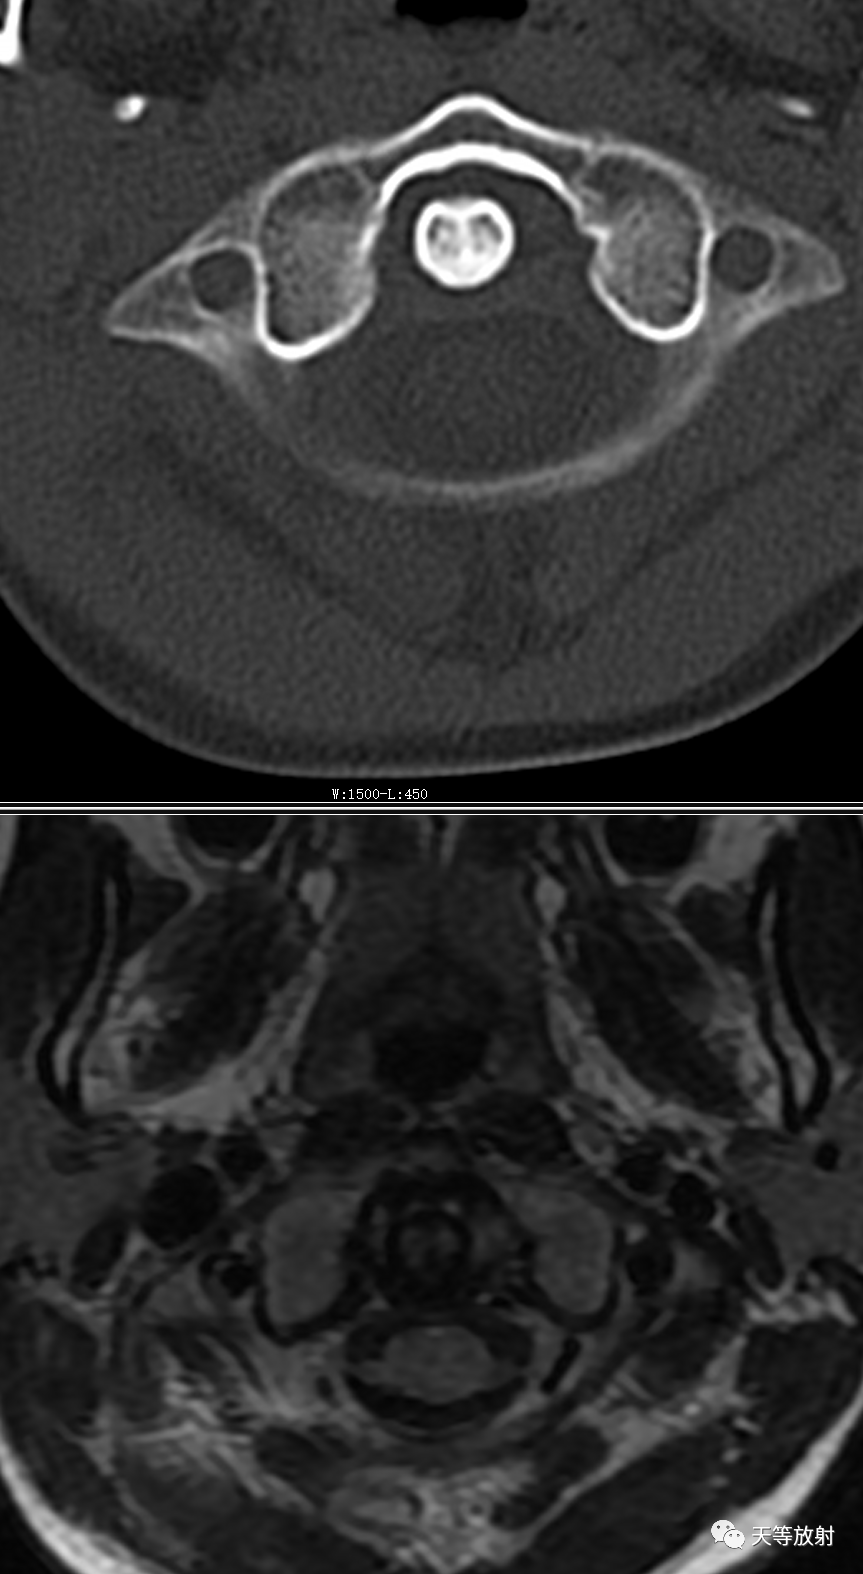

儿童,影像学上显示枢椎与环椎侧块间隙不等宽,呈左宽右窄。MRI环枢关节周围软组织无异常信号影。诊断:单纯性环枢关节半脱位。

病例2:男性,7岁。外伤。

上图:侧位环齿前间距 4mm。

上图:冠状位显示寰枢关节间隙不等宽,左宽右窄。